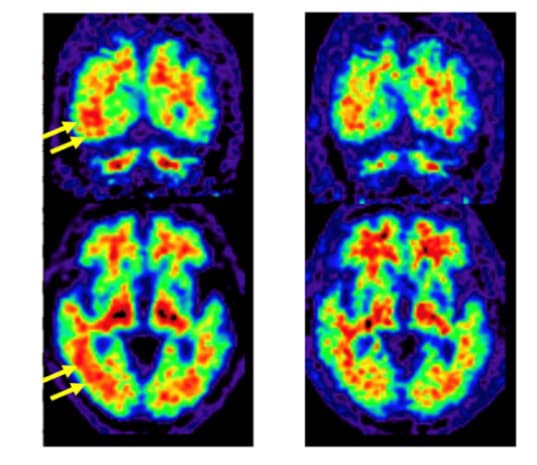

Left: Brain Amyloid PET Images Obtained with Conventional PET/CT System

Areas of PET tracer uptake indicated amyloid deposition. Yellow arrows show where PET tracer uptake appeared to extend to the gray matter of the brain (red areas extend to the surface of brain). Based on this, the gray matter was considered positive for amyloid accumulation.

Right: Brain Amyloid PET Images Obtained with BresTome

Images show that PET tracer uptake did not extend to gray matter (red areas do not extend to the surface of brain), which conflicts with the positive amyloid findings of the conventional PET/CT system.